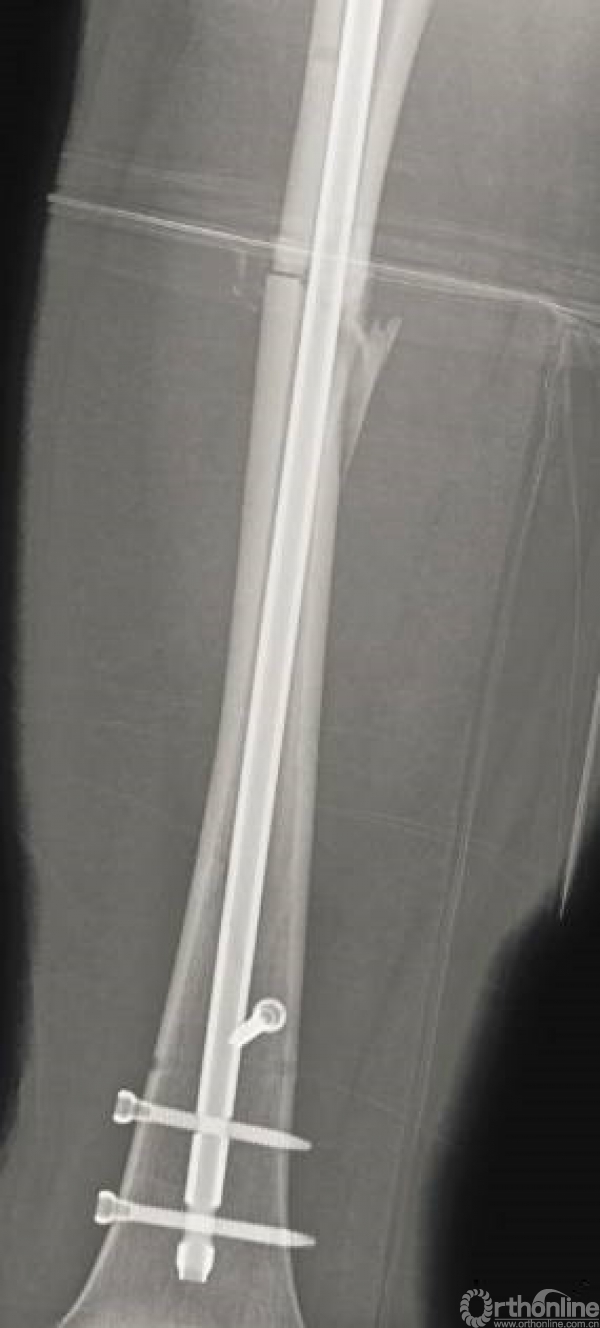

术后